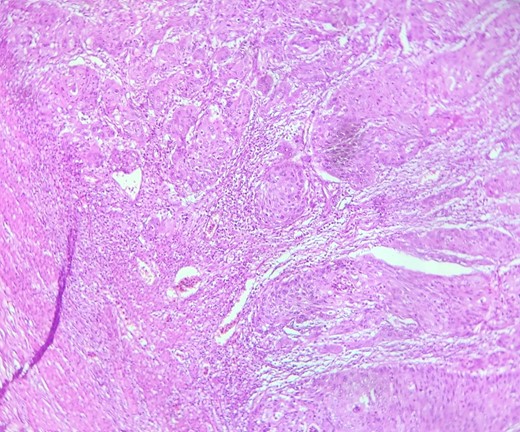

HE section: The tumor cells are so poorly differentiated that it is difficult to tell what the cell of origin is. The cells are discohesive with bizarre looking nuclei (×400).